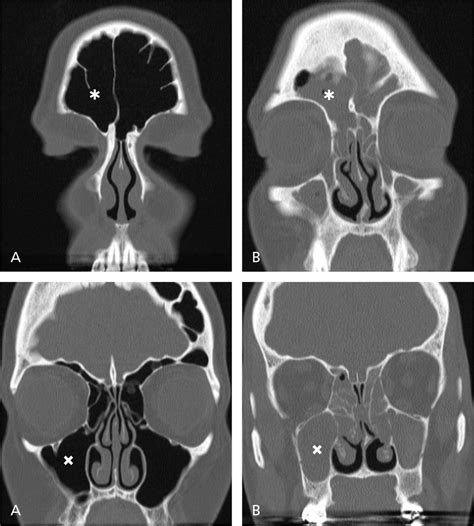

If you have been suffering from persistent sinus pressure, chronic congestion, or mysterious facial pain, your healthcare provider may recommend a Nasal CT scan to get a clearer picture of what is happening inside your nasal passages. This specialized imaging procedure is a cornerstone of modern otolaryngology, providing doctors with high-resolution, three-dimensional views of the complex structures within your nose and paranasal sinuses. Unlike a standard X-ray, which offers a two-dimensional look, a computed tomography (CT) scan provides detailed cross-sectional images, allowing specialists to pinpoint inflammation, structural abnormalities, or obstructions with remarkable accuracy.

A Nasal CT scan, often referred to as a sinus CT scan, is a non-invasive diagnostic tool that uses X-ray technology paired with advanced computer processing to create detailed images of your sinus cavities and nasal anatomy. When you undergo this scan, you will lie on a table that slides into a doughnut-shaped machine. The scanner rotates around your head, capturing multiple images from different angles to construct a comprehensive view of the area.

The primary purpose of this imaging is to assist ear, nose, and throat (ENT) specialists in diagnosing conditions that cannot be easily visualized during a routine physical examination. Because the sinuses are deep within the skull, traditional physical inspections only show a small portion of the nasal cavity. A CT scan, however, reveals the entire network of sinuses, highlighting potential issues that may require medical or surgical intervention.

Interpreting the Results

Once the images are captured, a radiologist will review them and generate a report. They look for specific markers of health, such as clear, air-filled sinus cavities, versus signs of pathology, such as fluid accumulation, mucosal thickening, or bone erosion. Your ENT specialist will then combine these results with your clinical symptoms to make a definitive diagnosis.

It is important to remember that a Nasal CT scan report is only one piece of the puzzle. An abnormal result does not always indicate a serious condition; for instance, some mucosal thickening might be the result of a mild, lingering seasonal allergy. Your doctor will interpret the findings within the context of your overall health history.